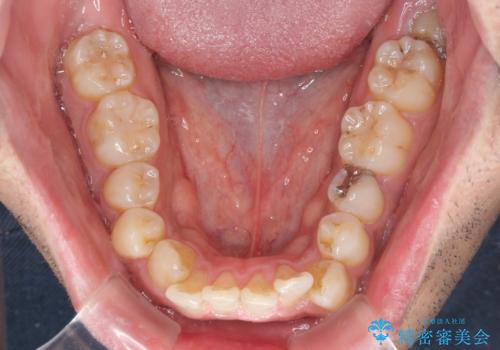

- 上下前歯部の叢生を気にして来院された患者様です。

レントゲン撮影により、右上奥歯が折れていることが分かりました。

患者様自身も何となく違和感を覚えていたとのことで、インプラント補綴治療を行うこととしました。

歯列不正は比較的軽微であったので、インビザラインによる矯正治療とし、矯正治療中にタイミングを見て抜歯とインプラント埋入を行う予定としました。